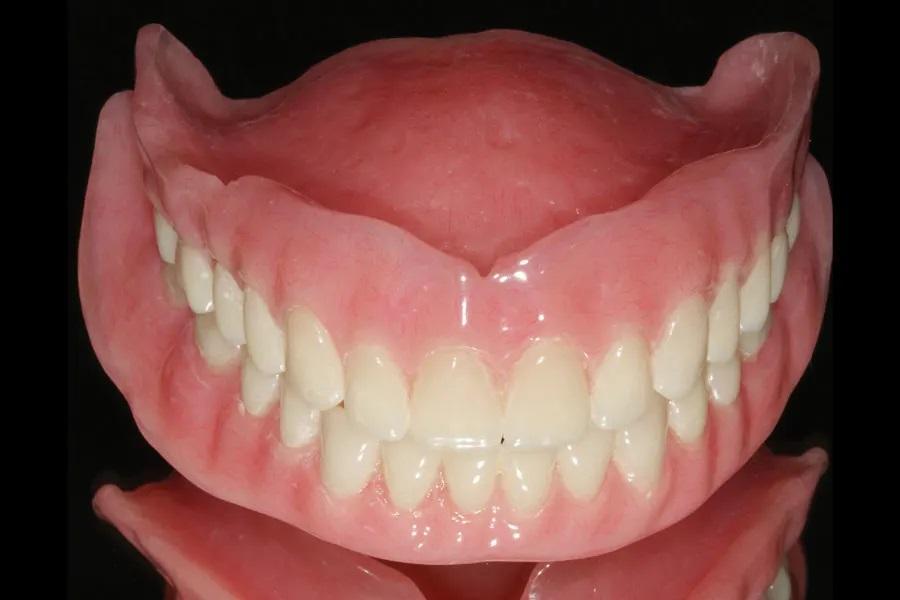

Процесс изготовления переходных и окончательных зубных протезов был начат с помощью 3D-интраорального оптического сканирования в середине февраля 2020 года и завершен во время пандемии COVID, когда в начале марта 2021 года были доставлены окончательные зубные протезы (Фото 8 и Фото 9). Пациентка посещала кабинет врача в общей сложности 10 раз, включая два отдельных хирургических визита (по одному на каждую дугу) и все послеоперационные и корректирующие визиты. Это также включало в себя изготовление и поставку временных зубных протезов, заживление мягких и твердых тканей, функциональные оттиски и поставку окончательных зубных протезов. Для сравнения, традиционное поэтапное удаление боковых зубов, регистрация данных и обычные слепки для временных протезов привели бы к гораздо большему количеству посещений, и пациентке пришлось бы длительное время терпеть неудобства, связанные с отсутствием большинства зубов, пока изготавливались временные протезы.

Фото 8: Окончательные протезы.